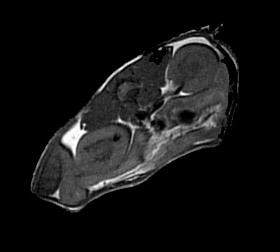

The aim of the course is to give the participants knowledge on the principles, the theory and practical use of MRI. The theoretical part of the course will cover multimodal imaging and the theoretical aspects of MRI. The participants will get hands-on training on the instrument in the practical part and learn about basic image analysis of MR images. After the course, the participants should be able to understand how to plan and perform MRI experiments on small animals.